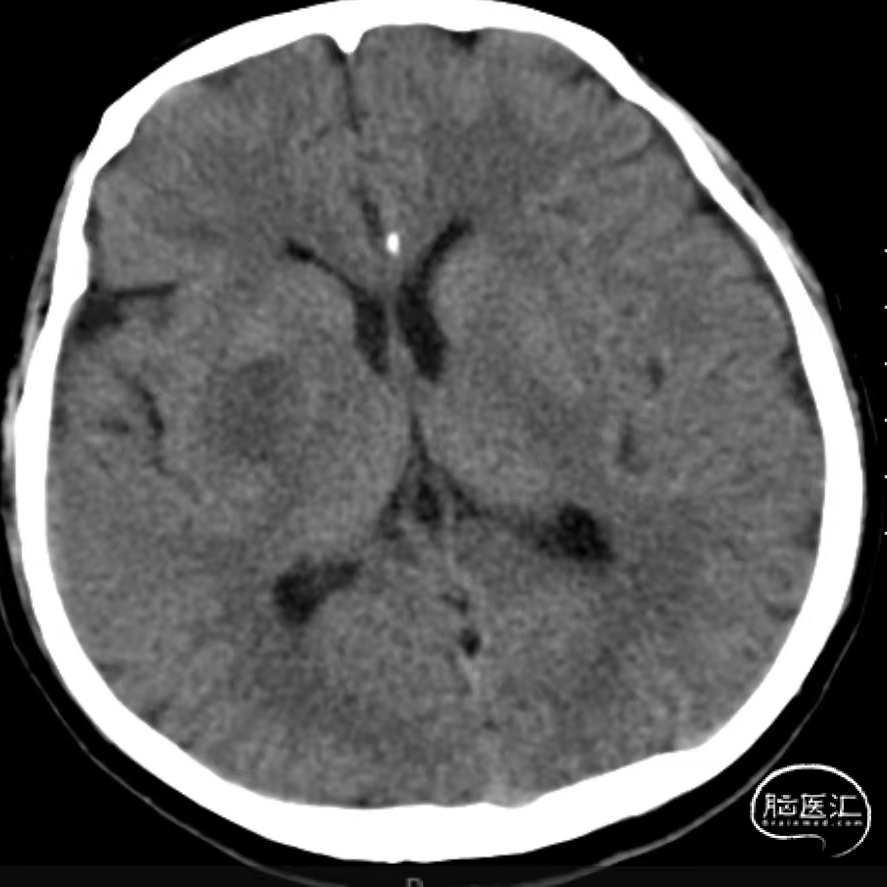

入院时CT:ASPECTS 9分(L1)。

术后即刻复查CT,未见出血及造影剂渗出。